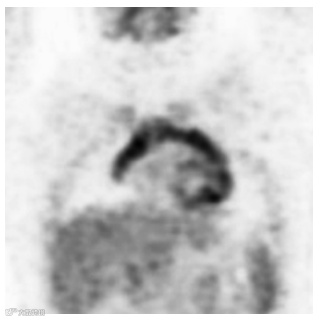

正常胃肠道对FDG的摄取变异很大,范围从轻微到强烈,呈局灶性、弥漫性或节段性分布。胃肠道对FDG摄取的原理尚不完全清楚,可能由多种因素引起。它可能与活跃的平滑肌、活跃的粘膜、吞咽的分泌物或微生物摄取有关。食管摄取可以注意到脊柱前部有轻微的线性摄取,在矢状面上看得最清楚(图8)。患有反流性食管炎或放射治疗后食管炎的患者,食管沿线会出现明显的摄取。患有食管裂孔疝和巴雷特食管的患者,远端食管的摄取也可能增加。通常可发现与胃壁相对应的曲线均匀摄取(图9)。如果胃部收缩,则可以看到一个圆形的中等活动区域。胃部摄取通常较轻,但更强烈的摄取可能与幽门螺杆菌感染有关。

图8. 矢状FDG PET 扫描 (a) 和融合PET/CT图像 (b) 显示胸椎前部线性18F FDG 摄取 (a),此发现与正常食管 (b) 相对应。